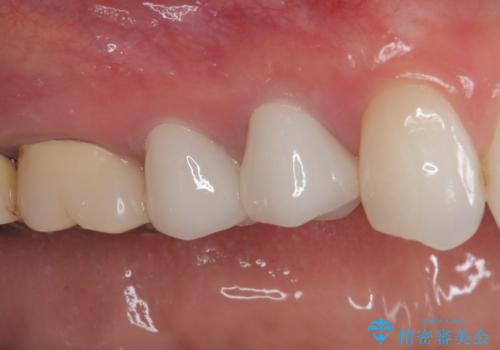

色がやや白いと感じましたが、ご自身でホームホワイトニングをされているそうで、今後周辺の歯を白くしていくとのことでした。

初回の根管治療で痛みや違和感は消退したため、その後は速やかに補綴治療を行いました。